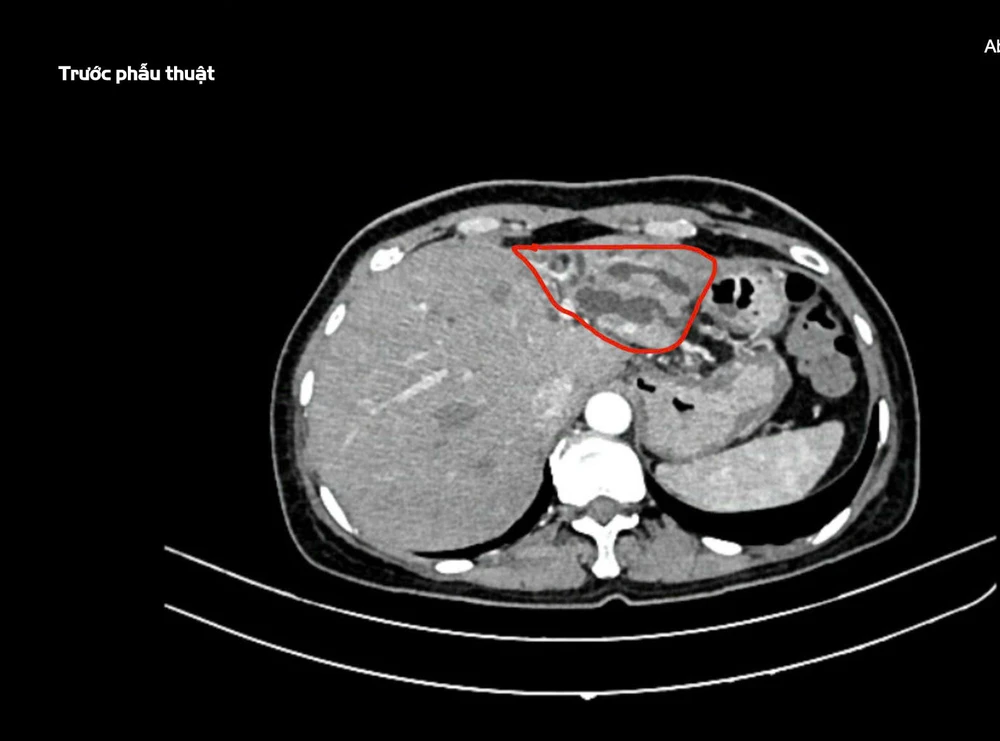

Hình ảnh nhiễm trùng đường mật do sỏi gan thùy trái, trước phẫu thuật. Ành: BVCC

Qua thăm khám lâm sàng và chẩn đoán hình ảnh, các bác sĩ phát hiện bệnh nhân bị nhiễm trùng đường mật do sỏi gan thùy trái, biến chứng viêm teo thùy trái gan trên nền bệnh đái tháo đường type II.